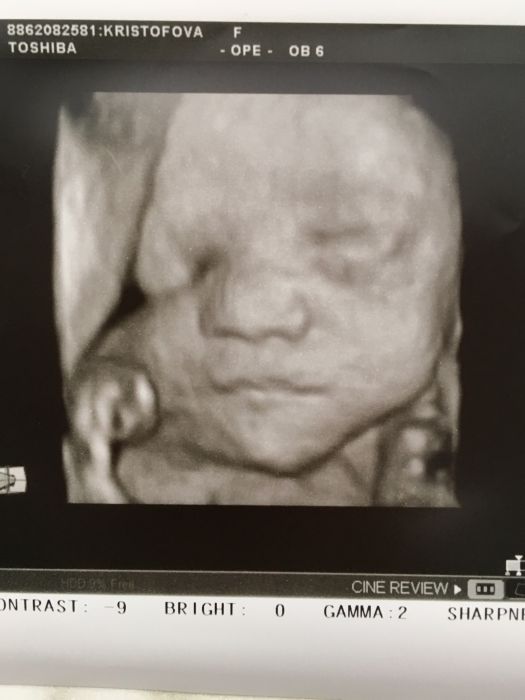

Holky tak hemeroidy me taky začaly trápit :-( sice to nějak extra nebolí nebo teda bolel mě jeden ten praskl a ulevilo se mi , ale teď tam mám už asi 3 :-( koupila jsem si gel z dubové kůry a uvidím kontrolu mám až za dva týdny .. Holky tak tady přikládám fotečku já . Dneska jsem se byla zapsat v porodnici a úplná náhoda sestřička co to normálně dělá byla nemocná tak jí zastupovala jiná z 3D UT tak jsem se zapsala a pak jí “drze “ samo , že mile říkám jestli by byla tak hodná a neudělala by mi fotku obličeje a ona , že v téhle fázi těhu už tam nejde nic moc vidět, že už je Drobek moc veliký na 3D , ale že to zkusí no a překvapivě i ona byla překvapená to šlo vidět krásně ;-) je teda hodně podobný Samíkovi tak uvidíme nakonec :-D

[1063978] krásné miminko

[1063978] Veru krásná fotecka